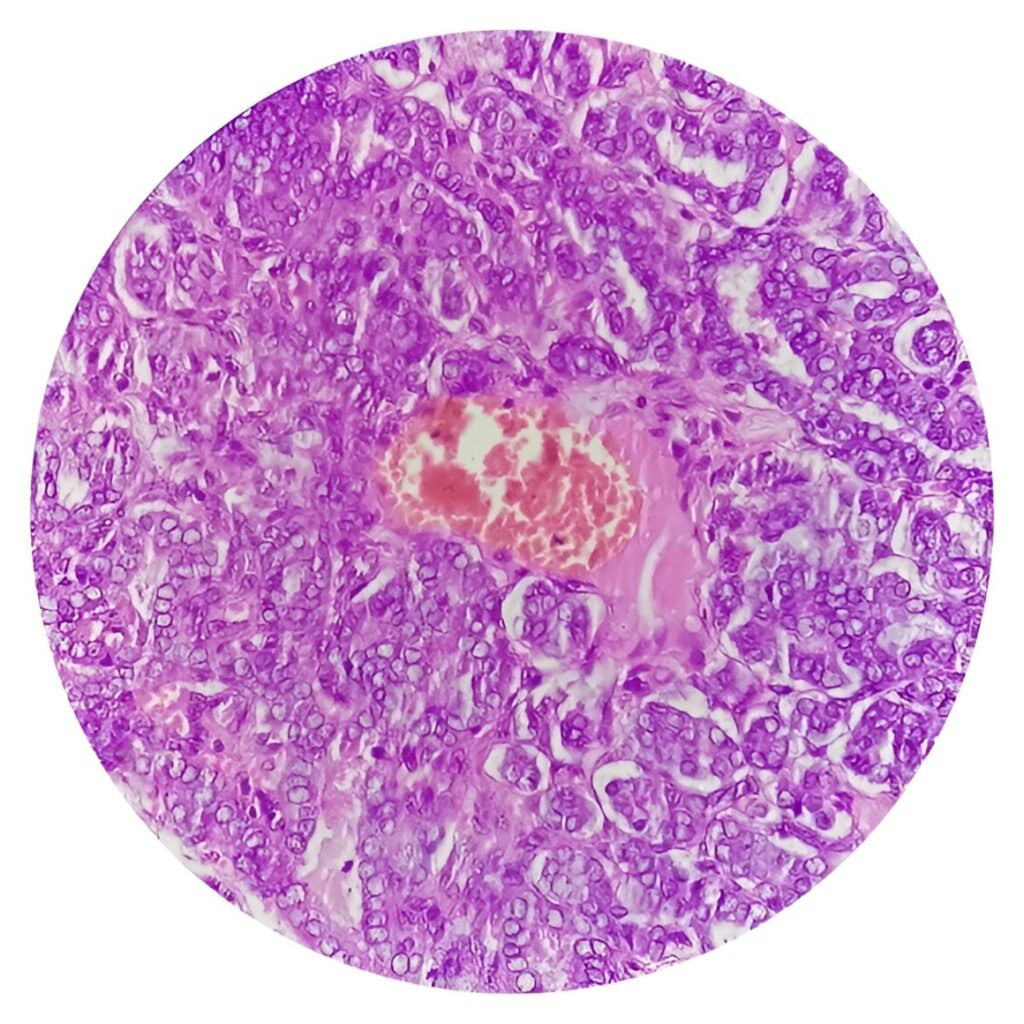

Head and neck squamous cell carcinoma emerges as the primary cancer type and starts from the cells covering the head and neck regions. Accurate disease detection followed by appropriate medical help enhance both the chances of recovery and patient health benefits.

Diagnosis and Specifications for Testing Cancer

- Biopsy: We perform a tissue examination to ensure the patient has cancer.